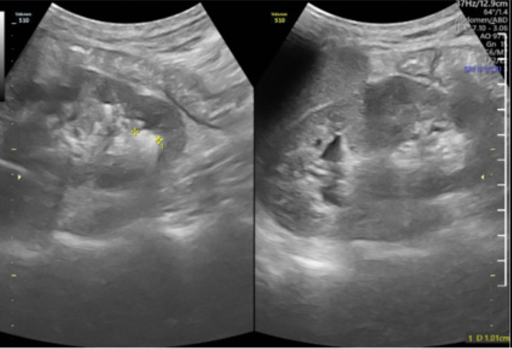

Vừa qua, khoa Ngoại, Bệnh viện Đa khoa MEDLATEC đã điều trị thành công ca bệnh sỏi thận bằng phương pháp tán sỏi qua da bằng đường hầm nhỏ. Đây được coi là phương pháp “vàng” trong điều trị sỏi thận, sỏi niệu quản nhờ những ưu điểm vượt trội mang lại cho người bệnh trong quá trình điều trị và hồi...